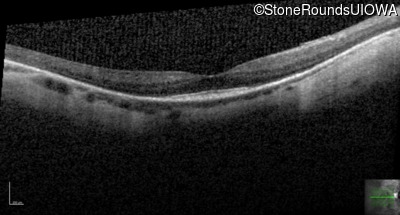

Optical Coherence Tomography - Left - 20/80

Exemplar / OCT Stack

OCT Stack